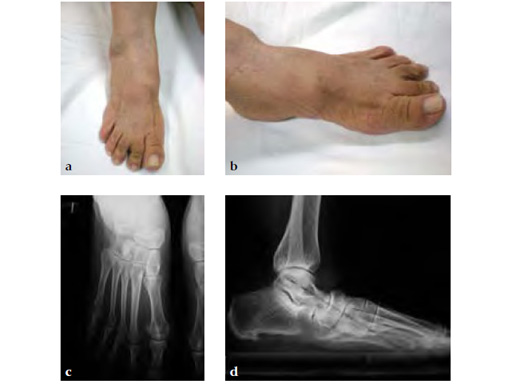

Case 1: 62-year-old white female with right stage II posterior tibial tendon insufficiency and II and III overload due to medial cuneiform first metatarsal joint instability treated with UCBL for 6 months after she complained of severe pain and increasing swelling

Case provided by Juan Bernardo Gerstner Garcs, Cali, Colombia

A medial displacement osteotomy of the calcaneus and transfer of the tendon of the flexor digitorum longus to the navicular fixed with an interference screw were performed (see Fig 2a-c). A fusion of the first medial cuneiformmetatarsal I, II, and III modified. Weil osteotomy was performed as well.

The talar axis is aligned to the midshaft of the first metatarsal (see Fig 3a-d).

Stage II of her left posterior tendon dysfunction and tarso/metatarsal, instability visible on x-ray (see Fig 1a-c).